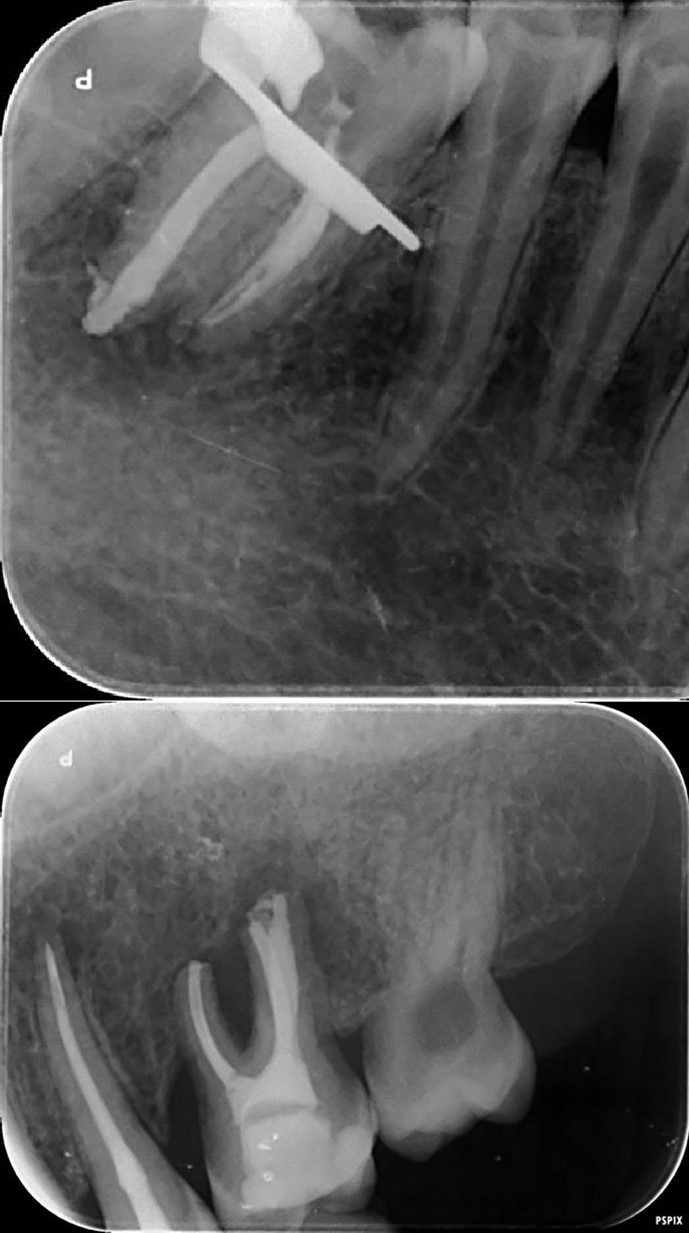

Complete healing of periapical lesions and treatment of teeth 26 and 16 with advanced endo-perio lesions posed challenges due to the patient’s delayed supplementation. In this case, surgical endodontic procedures and the extraction of teeth with advanced endo-perio lesions were considered risky because of the underlying metabolic healing impairment. Figure 3

Figure 3.6. 7, 8, 9, and 10 showing postoperative periapical radiographs of these endodontic treatments.